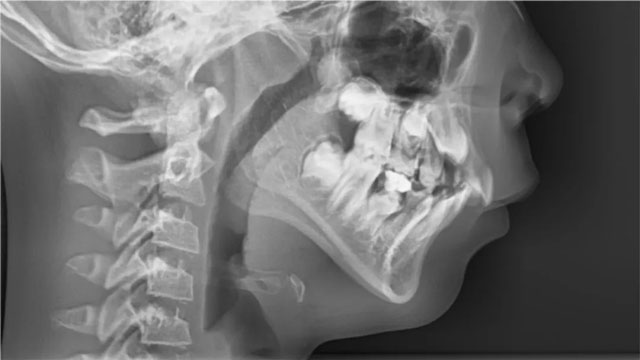

这次就诊和以往有所不同,除了拍片和检查,关医生还仔细查看了他们夫妻的面型,告诉他们诊断结果是:中重度深覆盖、深覆合,轻度下巴后缩。

随后,关医生分析了原因:“牙齿和面型问题受遗传因素影响很大,孩子应该是遗传了爸爸。先天因素加上长期的口呼吸,造成了现在这个情况。”从未关注过自己下巴的彤彤爸爸照了下镜子,有点尴尬。妈妈补充说彤彤奶奶也有这个问题,有严重的龅牙,嘴很突。

关禹哲医生:彤彤换牙偏晚偏慢,门牙牙根还没发育好,如果做矫形,治疗周期会很长,加力不合适会影响到牙根发育;从她的年龄和口颌系统发育阶段来看,今后做功能矫形的时间还很充裕。所以,对她来说当下就佩戴功能矫治器不是必须的,且弊大于利。彤彤正处于下颌骨发育高峰期,经过半年的肌功能训练,深覆盖、深覆合和下巴后缩都得到了明显改善,达到了治疗目的。当然,彤彤的情况只是个例。

关禹哲医生:下巴后缩属于II类错颌畸形,原则上提倡早期干预,但早期干预也需要满足一定的条件,包括牙根发育是否完成,能否移动,后缩是否严重,年龄因素等。如果不能满足以上条件,可能涉及过早、过度治疗,治疗后可能出现反弹的情况。